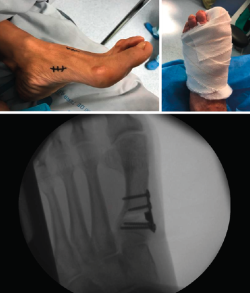

Figura 5. Caso clínico de osteotomía de cierre (radiología preoperatoria y control a los 4 años).

En las Figuras 4 y 5 se muestra un ejemplo intervenido de osteotomía de apertura y cierre.

Figura 3. Detalles quirúrgicos de la osteotomía de cierre lateral.